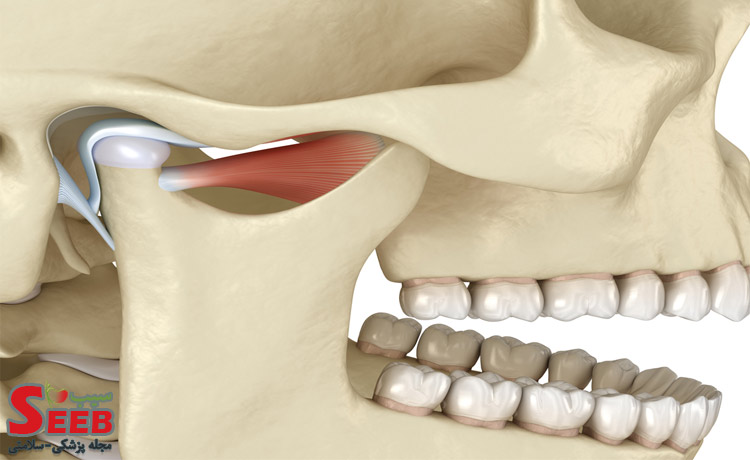

تابناک رضوی: دندان درد عصبی یکی از عوارض اختلال مفصل فکی گیجگاهی (TMJ) است. مفصل فکی گیجگاهی به نقطه اتصال استخوان جمجمه و فک گفته میشود. این مفصل به شما اجازه جویدن، حرف زدن، خواندن و غیره را میدهد اگر بدون هیچ دلیل موجه دیگری در این ناحیه احساس درد میکنید، به احتمال زیاد به اختلال درد مفصل فکی گیجگاهی مبتلا شدهاید.

اختلال مفصل فکی گیجگاهی ممکن است ناشی از برخی مشکلات فیزیکی باشد که از طریق رادیوگرافی یا MRI قابل تشخیص خواهد بود. اما به غیر از مشکلات فیزیکی، اضطراب و استرس نیز سبب اختلال مفصل فک گیجگاهی خواهد شد که ممکن است عوارضی مثل دندان درد عصبی، فک درد عصبی و یا درد عصبی صورت را به همراه داشته باشد.

فشار دادن یا سابیدن دندانها روی هم سبب فعال شدن عضلات فک و صورت شده و باعث کار کردن و یا انقباض و انبساط این ماهیچهها میشود. در ضمن مفصل گیجگاهی فکی که محل اتصال فک پایین و بالا است هم در این پروسه فشار دادن دندان ها روی هم دچار فرسایش و فشار اضافی می شود.

عضلات فک و صورت و مفصل گیجگاهی فکی ما قادرند که فشارها در زمان غذا خوردن را تحمل کنند. این فشارها در حین غذا خوردن در طول شبانه روز معمولا ۱۵ تا ۲۰ دقیقه طول میکشد اما به دلیل استرس و فشار مداوم و همچنین دندان قروچه، عضلات فک و صورت و مفصل گیجگاهی ممکن است ۱۰ تا ۱۸ ساعت تحت فشار و فعالیت باشند و میتوان از آنها به عنوان علت درد کل دندانها یاد کرد.

این فشار و فعالیت بیش از حد عضلات صورت و مفصل فکی گیجگاهی سبب خستگی و فرسایش آنها شده و متعاقبا باعث دردهای فک و صورت و مفصل گیجگاهی می شود. این درد ناشی از التهاب و خستگی این عضلات و مفصل است.